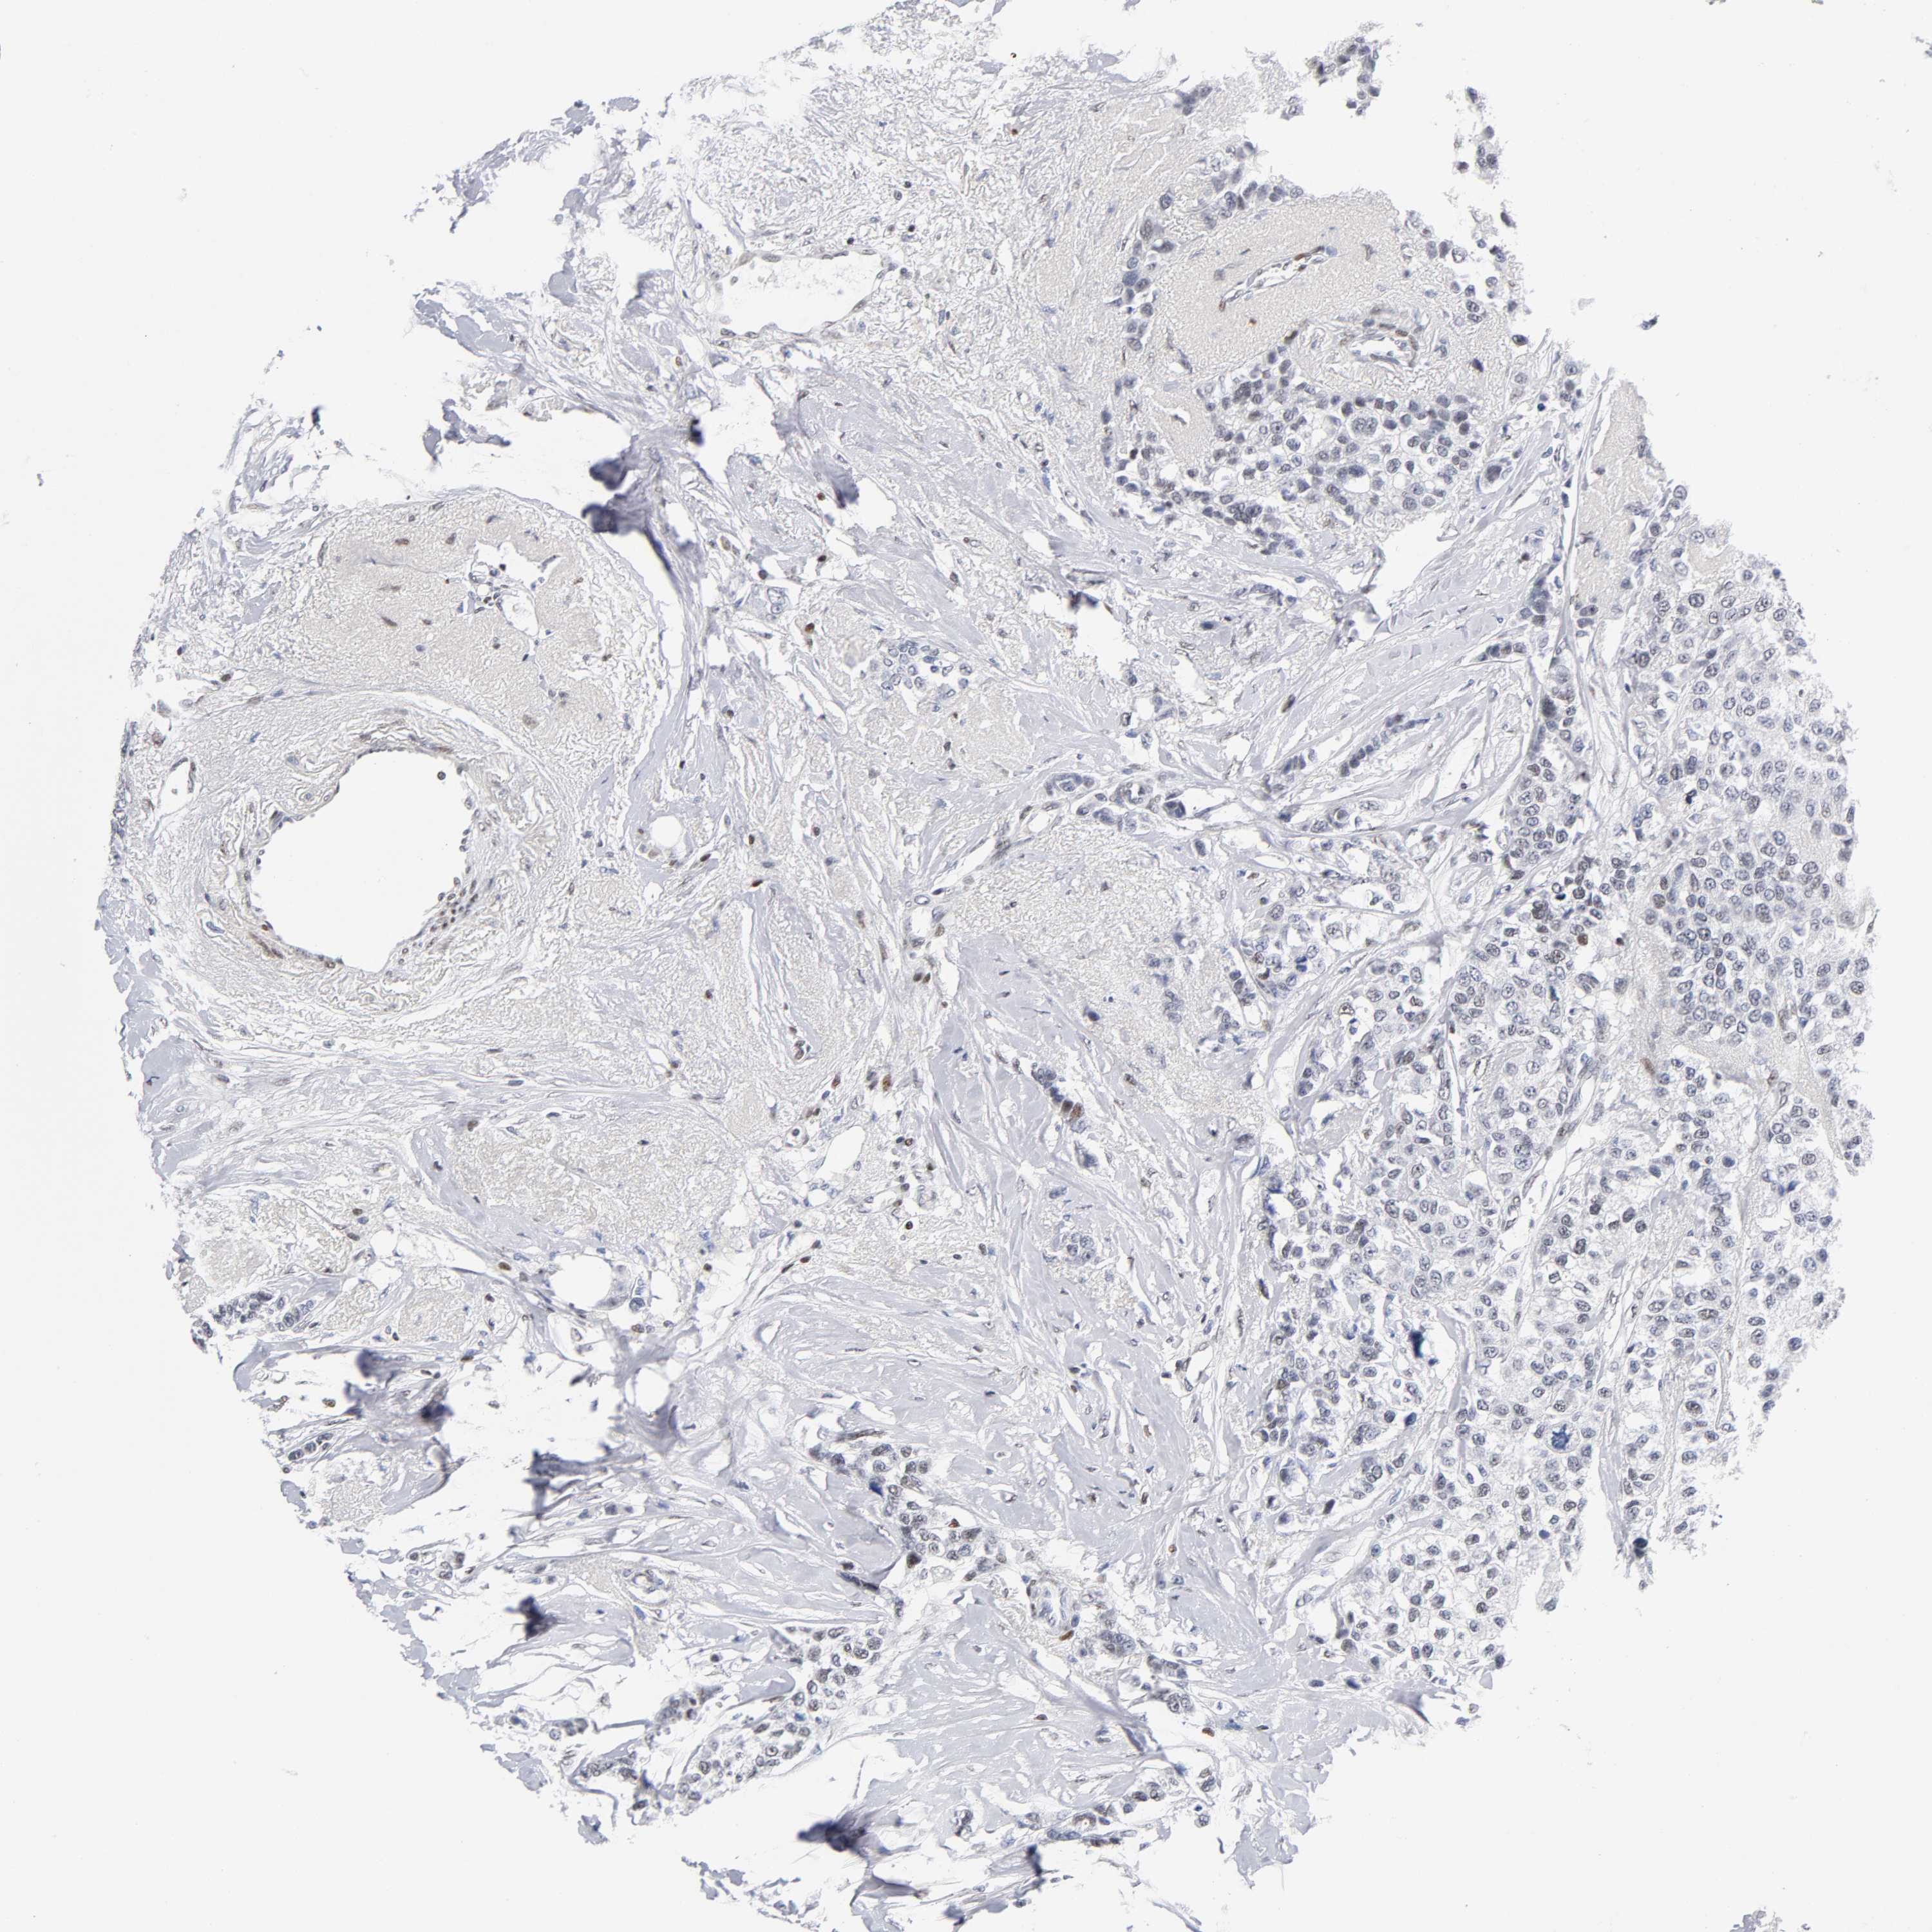

CANCER BREAST CANCER Show tissue menu

BRCA TCGA BRCA VALIDATION PROTEIN EXPRESSION

ANTIBODIES

AND

VALIDATION